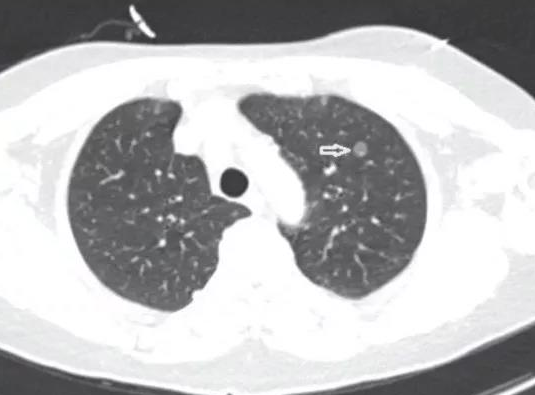

肺结节是一种影像学表现,不算是一种疾病,但它们确实有这样的表现,具有恶性倾向,因此患者非常紧张。肺结节一般为良性结节,大多由炎症、肺结核、尘肺等疾病引起,在肺部留下疤痕形成结节。

肺结节可以完全治愈。良性肺结节需要考虑多种疾病。例如肺炎、肺部真菌感染或结核病。如果是肺炎,经有效的抗生素治疗后,肺结节可以消失。

如果是肺结核,在标准化抗结核治疗后可以消失。此外,如果是由隐球菌感染等真菌感染引起,可以进行抗真菌治疗,大多数肺结节可以完全治愈。

肺结节也需要考虑恶性疾病,如早期肺癌。此类患者可以通过手术切除进行治疗。此外,如果是肺结节,考虑到晚期肺癌其他部位的转移,肺结节的治愈更为困难,应采用一些化疗或靶向治疗。